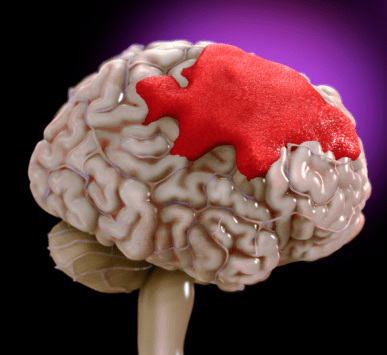

A dangerous condition referred to as an intracerebral hemorrhage occurs when blood leaks directly into brain tissue, often due to trauma, hypertension, or vascular abnormalities.

There is one type of stroke that results from internal bleeding in the brain, and it is referred to as a brain hemorrhage. t is usually caused by the bursting of a blood vessel